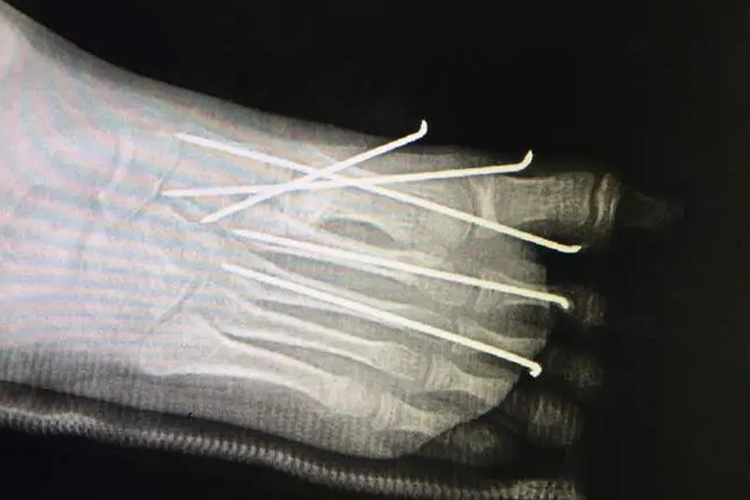

跖骨骨折克氏针固定为内固定术,多用于跖骨骨折切开复位术及切骨术。用一根克氏针自远骨折端的近端髓腔穿入,同时使跖趾关节尽量过伸,使钢针尾端退至骨折端,以保持骨折端的复位。本术式可以较好地保持骨折的解剖复位,比单纯外固定直接而有效,特别在防止骨折端的剪式或旋转性活动方面更为有效。